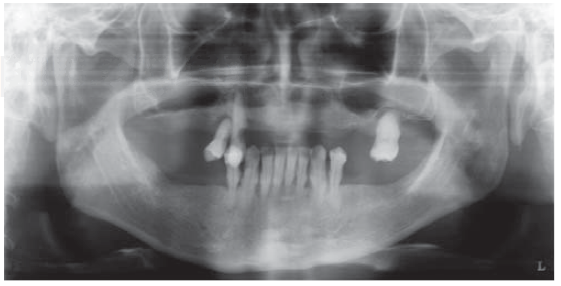

Radiographic examination

Radiographic examination revealed generalized horizontal bone resorption, pneumatization of both maxillary sinuses, caries in tooth 1.3, radio-lucid lesions at the height of periapex of teeth 1.3, 1.4, 2.6 and 4.4 (Figure 1).

Based on information harvested from clinical and radiographic examinations, the following diagnoses were established: severe generalized chronic periodontitis in tooth 1.3, dental abscesses in teeth 1.3, 1.4, 2.6 and 4.4 as well as upper and lower partial edentulism with upper alveolar ridge atrophy and bilateral maxillary sinuses pneumatization.